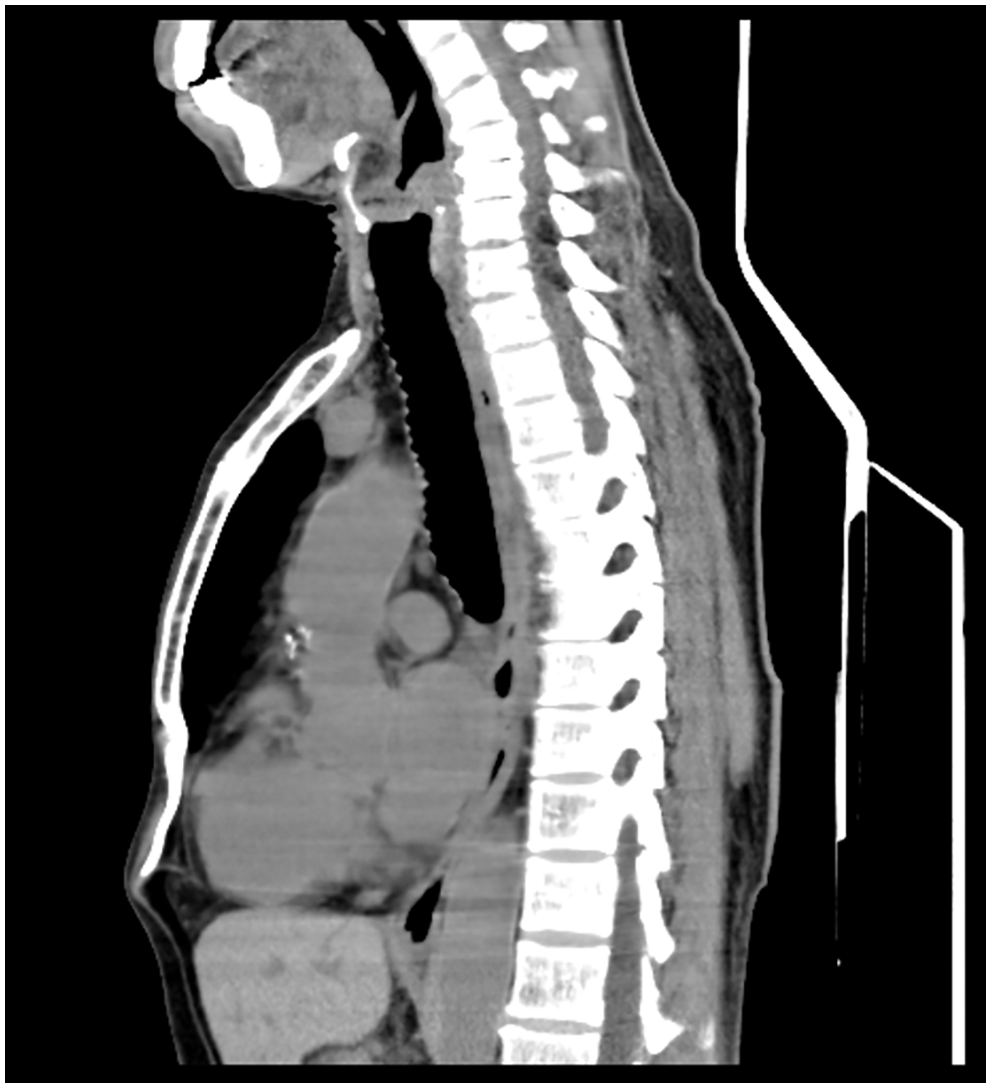

A 65-year-old man was referred to our hospital for investigation of atypical chest tightness of gradual onset over the previous 6 months. He denied weight loss, dysphagia, upper GI bleeding, reflux, or other symptoms. Blood and urine biochemistry showed almost normal results. However, transthoracic echocardiography revealed a solid echoic mass of approximately 16 cm behind the left atrium and significant compression of the left atrium. Chest computed tomography (CT) with contrast administration was performed. The examination was also completed by volume rendering reconstruction (VR) (Fig. 1) and revealed a solid mass of approximately 163 × 73 mm (the volume was 1308.92 mm3) visible behind the left atrium. The heart was compressed forward, the adjacent left atrium was significantly compressed, and the adjacent bronchi and esophagus were significantly compressed and displaced. A barium swallow study revealed that the lower esophagus was clearly shifted to the left under pressure, partially shifted forward in the left anterior oblique position, and shifted backward in the right anterior oblique position (Fig. 2). The barium meal passed smoothly. Considering that the patient had severe cardiac symptoms, thoracotomy was performed emergently. During the operation, the tumor was found to be approximately 17 cm in diameter and located in the posterior mediastinum, with unclear boundaries in some areas, abundant blood vessels on the surface, and cystic firmness in texture. The tumor was punctured with a thick needle to extract the internal fluid, which was bloody and mixed with sediment. After suction, the cyst wall was sutured and used for traction. The tumor wall was free along the edge of the tumor, with obvious oozing but no obvious blood-supplying artery. Because the source of the tumor was not known before the operation, the operation was very difficult. Further exploration on a subbase revealed that the tumor originated in the esophagus and had a short, wide pedicle on the lateral wall of the esophagus. Although the origin of the tumor has been clarified thus far, it is still difficult to completely remove the tumor. Fortunately, the entire tumor was finally removed with difficulty from meticulous operation. Postoperative pathological examination showed that the tumor was grayish yellow in section, had cystic firmness, was soft in quality and yellowish and sticky and frozen in appearance; part of the gray matter was broken, and part of the envelope was yellowish dark red. The diagnosis was an esophageal gastrointestinal stromal tumor with nuclear division <5/50 HPF (Fig. 3). The tumor basal margins were negative, and lymph node examination showed no cancer metastasis. Immunohistochemical indicators were as follows: SMA (−), S-100 (−), actin (+), desmin (−), PCK (−), EMA (−), VIM (+), CD34 (+), c-kit (+), Dog-1 (+), MDM-2 (+), CDK4 (−), and KI67 (+4%). After a multidisciplinary meeting, the patient received adjuvant therapy. Through multidisciplinary consultation, the patient received oral treatment with 400 mg of imatinib once daily after the operation and was closely followed up with chest CT scans (Fig. 4) or the barium esophagram every 6 months. After 3 years, the patient showed no sign of local recurrence with regular barium esophagram (Fig. 5), and no abnormally enlarged lymph nodes shadows were found on CT scans of the chest and abdomen performed during the follow-up.

Figure 4: The postoperative 16-slice computed tomographic scan of chest and epigastric examination showed that there was no shadow at the original mass occupying site